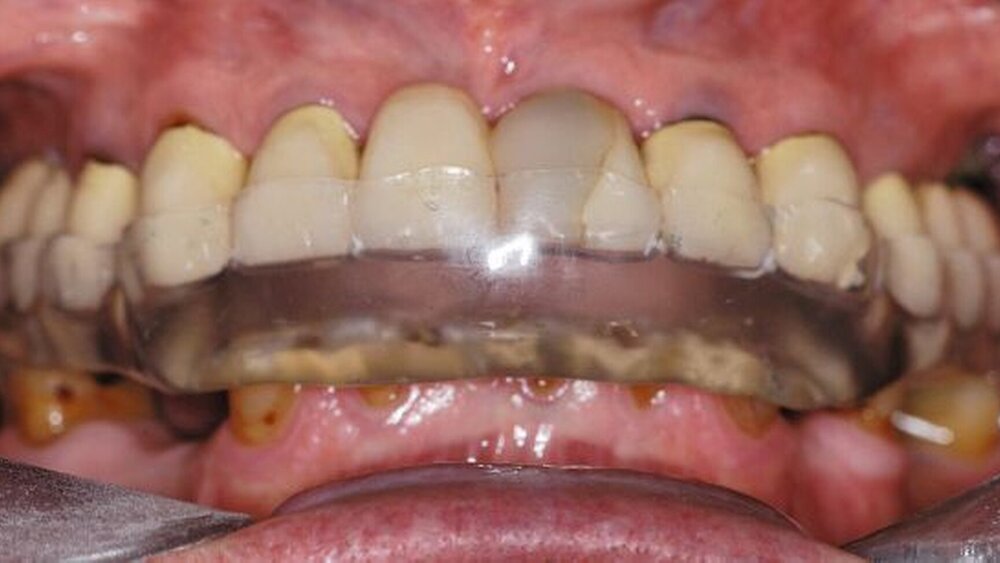

In der darauf folgenden Sitzung wurden alle Kronen und Brücken sowie die teleskopgetragene, partielle obere Prothese für einen Zeitraum von sieben Tagen zum Probetragen mittels eines Zements auf Zinkoxid-Eugenol-Basis eingegliedert. Dem Patienten sollte durch das Probetragen der Restaurationen beziehungsweise des angefertigten Zahnersatzes die Möglichkeit gegeben werden, sowohl die Funktion beim Essen und Sprechen als auch die Ästhetik im sozialen Umfeld zu testen. Ein erneutes Entnehmen der Restaurationen wäre – für den Fall notwendiger Korrekturen – somit ohne Weiteres möglich gewesen. Da der Patient sowohl die Funktion als auch die Ästhetik betreffend keine Änderungswünsche vorbrachte und auch keine neuerlichen Beschwerden aufgetreten waren, konnten die Restaurationen nach besagtem Tragezeitraum von sieben Tagen entnommen, gesäubert und mittels eines Glasionomerzements definitiv befestigt werden. Im Anschluss wurden erneut Situationsabformungen der Kiefer genommen und der Patient erhielt nach erneutem Checkbiss-Registrat, eine okklusal adjustierte Stabilisierungsschiene im Unterkiefer. Diese dient der Therapie der beschriebenen Bruxismusproblematik und gewährleistet einen langfristen Erfolg der eingegliederten prothetischen Restaurationen (Abbildungen 13a, 13b, 13c, 14, 15a, 15b, 15c).

Nach einer fünf Monate dauernden Funktionstherapie mit Stabilisierungschiene und initial begleitender manueller Therapie wurde aufgrund der vollständigen Beschwerdefreiheit mit den weitergehenden Behandlungsmaßnahmen begonnen. Zunächst wurde die Schiene im Bereich der Zähne 11/12 in zwei Teile separiert. Die Zähne des IV-Quadranten wurden mittels dentinadhäsiver Aufbaufüllungen rekonstruiert und – bei im II-Quadranten eingesetzter Schiene – reokkludiert. Nach Abschluss dieser Maßnahme wurde die Dentition im III-Quadranten auf die gleiche Weise aufgebaut und reokkludiert. Durch dieses Vorgehen war es möglich die Schienenokklusion, bei gleichzeitiger Anfertigung von dentinadhäsiven Aufbaufüllungen im Unterkiefer, auf diese zu übertragen, so dass der Patient auch ohne Schiene in identischer horizontaler und vertikaler Kieferrelation abgestützt war. Nach einem Zeitraum von 14 Tagen bestand noch immer vollständige Beschwerdefreiheit, so dass beschlossen wurde, mit der Behandlung fortzufahren.